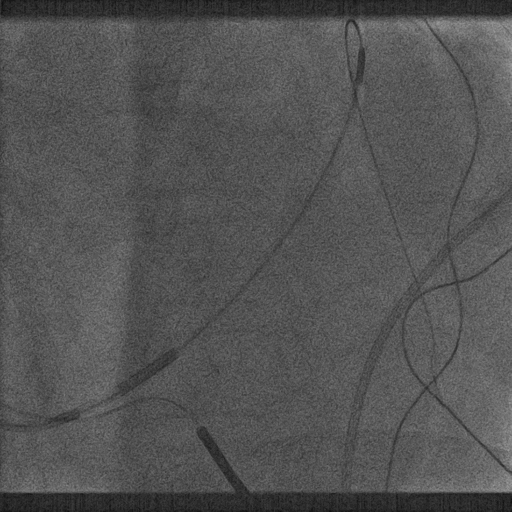

鞘中鞘进入靶血管

超选造影

沿鞘中鞘进四极电极